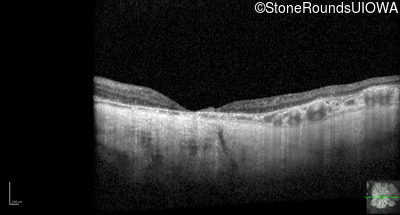

Optical Coherence Tomography - Left - 20/500

Exemplar / OCT Stack

OCT Stack